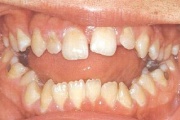

Turritavad ülemised lõikehambad.

ruumipuudus eesmiste hammaste osas